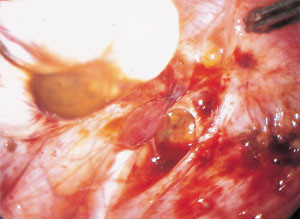

Endometrios är en kronisk sjukdom som drabbar 5 – 10 procent av kvinnor i reproduktiv ålder och förorsakar i många fall mycket svåra smärtor och reducerad livskvalitet. Ett centralt fenomen i sjukdomens patofysiologi är förmodligen implantation och inväxt på ektopiska ställen av avstötta endometrieceller, vilka initialt ger upphov till en lokal inflammation (fig 1). Möjligheten för endometriefragment att implantera tycks bero på att de lymfocyter, s k NK-celler (natural killer cells), som normalt känner igen och bryter ner bl a endometrieceller (liksom t ex virusinfekterade celler och tumörceller) utan föregående sensitisering, hos vissa kvinnor har en defekt cytotoxicitet (1).

I den kaskad av inflammatoriska processer som initieras i samband med adhesionen och implantationen frisätts olika substanser av vilka en del är smärtframkallande. Denna process initieras varje gång bäckenhålan exponeras för en retrograd menstruation. Frekventa, rikliga och/eller långdragna menstruationer har visat sig vara relaterade till förekomsten av endometrios, men å andra sidan har tidigare användning av p-piller, som minskar blödningsvolymen, eller IUD (intra-uterine device), som kan öka densamma, inte visat sig vara specifikt relaterade till förekomst av endometrios (2). Det annorlunda kontraktionsmönstret i myometriet med hyperperistaltik, som påvisats hos kvinnor med endometrios (3) bidrar sannolikt genom att öka volymen av retrograd blödning. Symtomet under denna fas av sjukdomen är huvudsakligen menstruationsrelaterad bäckensmärta. Så småningom övergår den akuta inflammationen i en kronisk form med fibrosbildning runt och in i härdarna (fig 2). När endometrioshärden inkapslats i fibros blir produktionen och expositionen av inflammationsmedierande substanser begränsad. Samtidigt som vissa härdar fibrosomvandlas uppstår dock nya härdar. På så sätt tycks såväl akut som kronisk inflammation pågå parallellt i lilla bäckenet hos många kvinnor. Endometriosvävnaden har en potential att växa in i omgivningen (fig 3), och denna invasiva växt, liksom fibrosen, kan involvera afferenta nerver, vilket resulterar i mer eller mindre kronisk smärta.